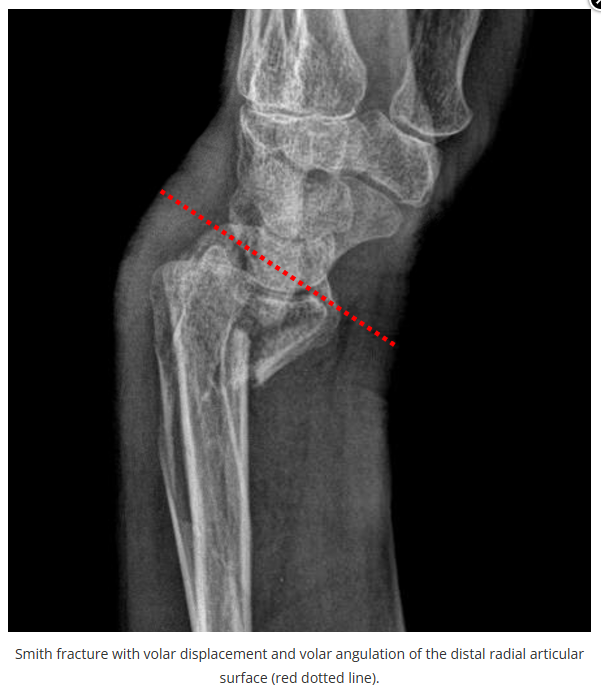

这些腕与手的骨折X线片如果没有标注箭头,你还能识别出来吗?

X线读片是骨科医生的基本功。

今天是腕部与手的X线片。所有X线片都

带有标注和说明

,可以选择长按图片,

自动翻译相关说明

。